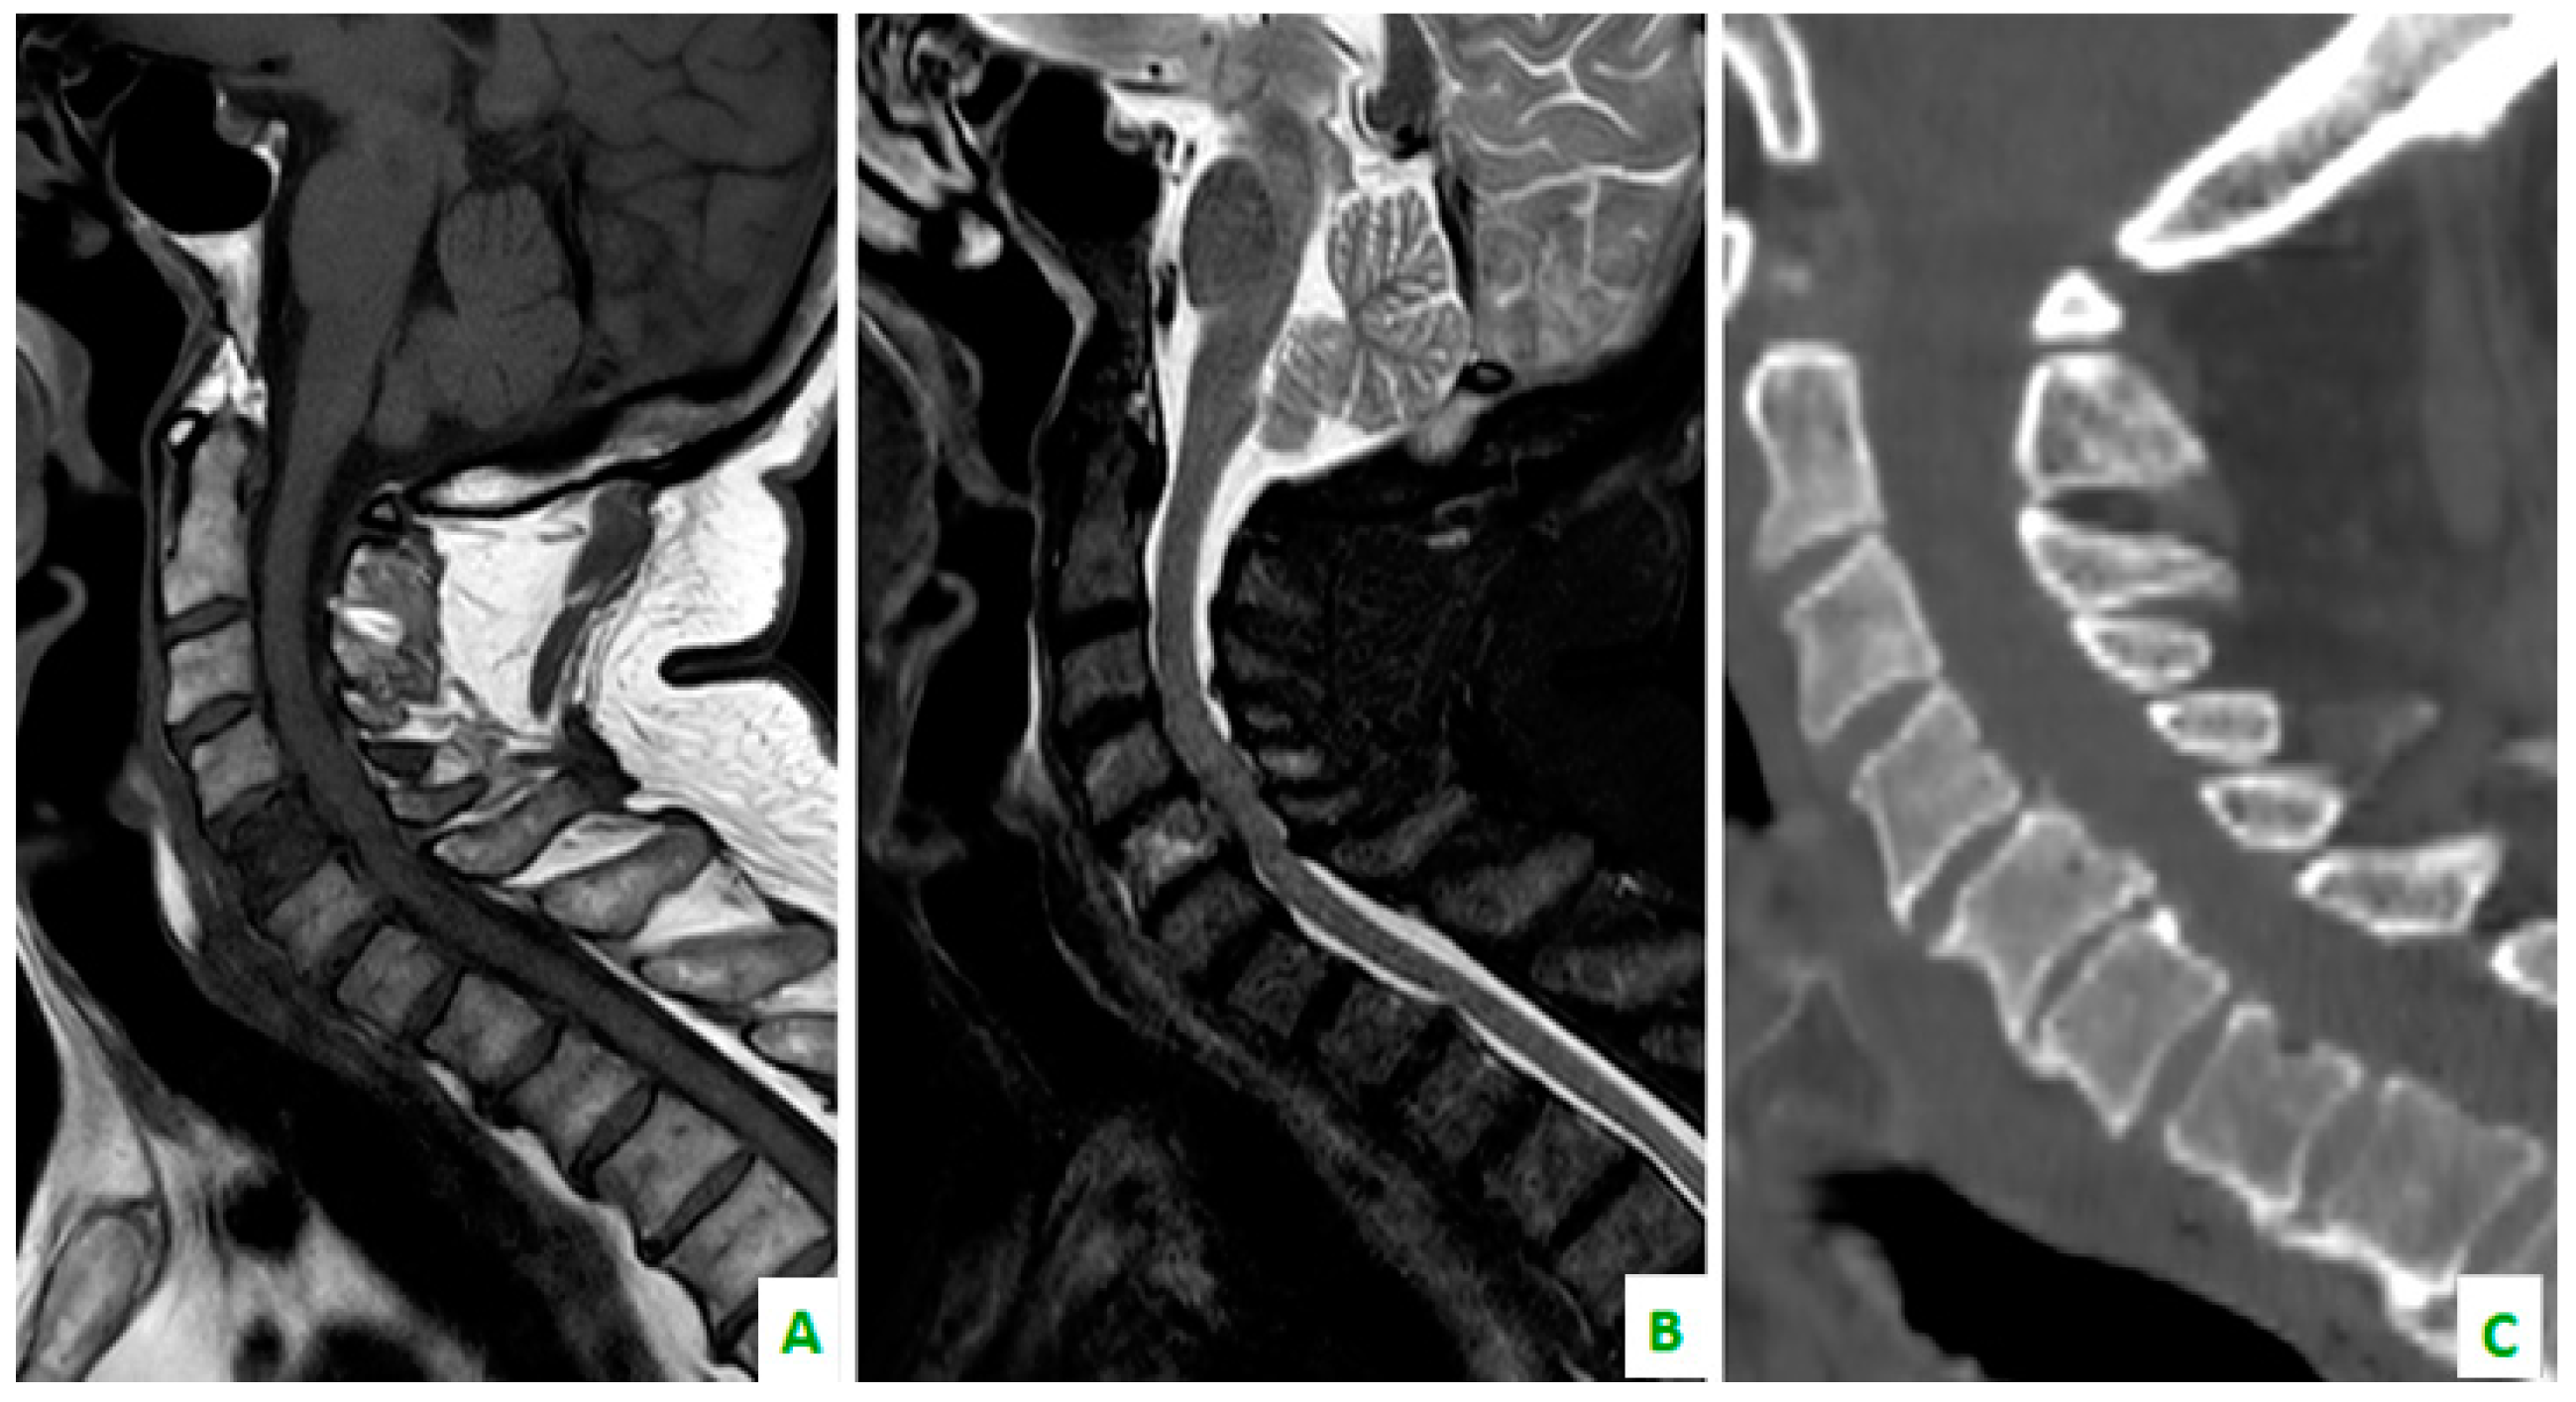

Figure 4. Focus on the red circles: (A) DIXON T2 weighted in the sagittal plane showing bone cervical metastasis (C5) (B) a low apparent diffusion coefficient (ADC) value in the same level, and (C) a restriction of diffusivity.

Skeletal metastases, which are predominantly osteolytic, localize in the spine in 50% of patients. This the most common area of localization, followed by the ribs (27.1%), ilium (10%), sacrum (7.1%), femur (5.7%), and the humerus, scapula, and sternum (2.9%). This is according to a retrospective study by Tsuya et al. [27] (Figure 3, Figure 4 and Figure 5).